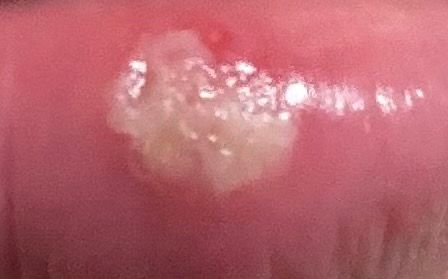

• 1번 째 사진

• 사진 두 장 확인했습니다.

첫 번째 사진에서는 입술 안쪽 점막에 흰색 궤양성 병변이 보이고, 두 번째 사진에서는 입술 경계부(피부와 점막이 만나는 부위)에 붉은 기운과 함께 노란 삼출물이 있는 병변이 확인됩니다.

결론부터 말씀드리면 피부과 선생님과 약사님의 판단이 맞을 가능성이 높습니다. 두 병변의 위치와 형태를 보면 구강 내 아프타성 궤양(aphthous ulcer), 즉 흔히 말하는 입병과 더 일치합니다. 헤르페스(herpes labialis)는 보통 입술 바깥쪽 피부, 즉 점막이 아닌 피부 면에 작은 수포들이 무리지어 나타나고 터지면서 딱지가 생기는 경과를 보이며, 타는 듯한 통증이나 가려움이 먼저 느껴지는 경우가 많습니다.

다만 두 번째 사진의 입술 경계부 병변은 위치상 헤르페스가 생기는 부위와 겹치기는 합니다. 이미 항바이러스제를 처방받으셨다면 혹시 모를 상황에 대한 예방적 처방일 수 있고, 실제로 복용하시는 것이 나쁘지 않습니다.